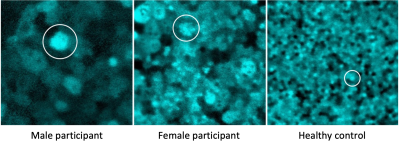

Three images of eyes with choroideremia showing enlarged RPE cells

Images of the retina showing enlarged RPE cells (circled) in a male (left) and female (center) study participants with choroideremia compared to a healthy control (right). Credit: Johnny Tam/National Eye Institute.

“One major finding of our study was that the RPE cells are dramatically enlarged in males and females with choroideremia,” said Tam. “We were surprised to see many cells enlarged by as much as five-fold.”

Female participants in the study showed a mix of enlarged and healthier-looking RPE cells. This may explain why women with choroideremia have milder symptoms, according to Tam. Photoreceptor and blood vessel layers were less affected in both male and female study participants, suggesting that RPE disruption plays an important role in choroideremia.